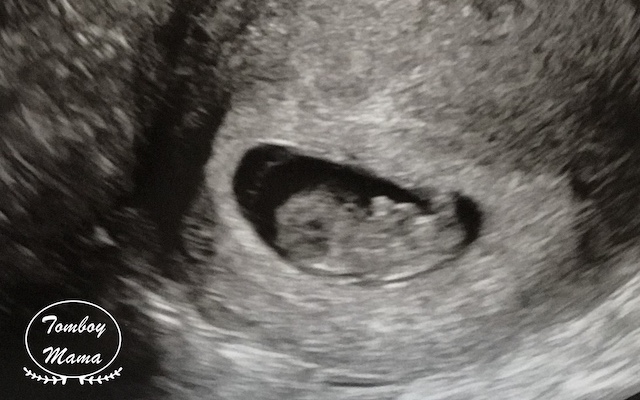

그렇게 튼튼이 모습을 별 설명 없이 보여주셨는데, 움직이길래 '움직인거에요?' 했다. 그러고나서는 감격에 벅차 눈물이 차올랐.. 다기 보다는, '오, 잘 살아있구나' 하는 생각이 들었다. 남편도 보아하니 감격보다는 신기함이 더 큰 것 같았다. 나중에 지나고나서 물어보니, SF 영화에서 보는 외계인 검사 장면ㅋㅋㅋㅋ-_- 같았다고 한다. 아기는 주수에 맞게 잘 크고 있다고 했다. 그리고나서 보여주신 아기 심장 뛰는 모습! 이때 '열심히 자라주고 있구나!' 하는 생각과 함께 책임감이 들면서 조금 뭉클했다. 우리는 이렇게 심장 소리는 듣지 못하고, 보기만 했다. :)

한국에서는 다들 5-6주차에 첫 초음파 진료받으면서 아기집을 보던데, 나는 9주차 넘어 이미 움직이고 있는 녀석을 보니 복합한 감정들이 하나하나 익숙해질 새 없이 올라왔다. 그래서인지 기다리고 기다리던 순간인데, 뭔가 너무 훅- 들어온 느낌. 아무래도 임신에 대한 확신이 100%는 아닌 때라, 그 순간에는 안도감 가장 컸던 것 같다.

아직 젤리곰 Gummy Bear 모습인 9주 2일차 튼튼이